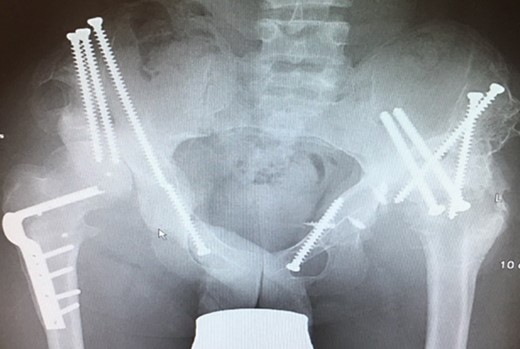

(A + B): (2019) (A) x ray of the pelvis after a 10 year follow up. The right head further migrated und subluxated and femoral head necrosis is visible, new bone formation at the ileum stabilizing the joint. At the left side high dislocation of the hip with fully necrosis of the head and ankylosis of the hip joint. (B) MRI showing hip effusion around the joint which is painless.

At this stage patient’s walking ability was already limited due to muscle weakness and rubbing in the hip joints, so we recommended no further walking and weight bearing. Further follow-up at 5 years (Fig. 7) and 10 years (Fig. 8A) until today showed radiologically complete absorption of the left femoral head and the right hip continuously moving cranially creating a false acetabulum and a flattened femoral head. At final follow up the patient was in a wheel chair but able to bend both hips up to 110 degrees without noticeable pain, he could stand up with help for a short time and showed a massive Charcot joint with effusion (Fig. 8B) of the right hip without further clinical implications.